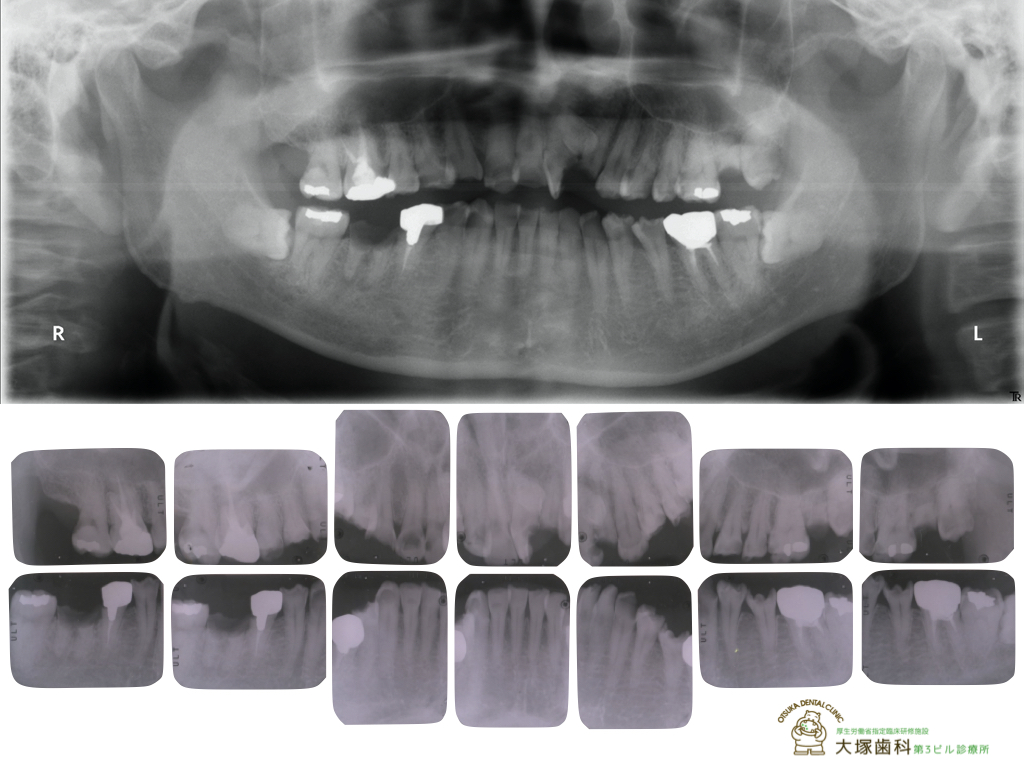

[レントゲン術前]